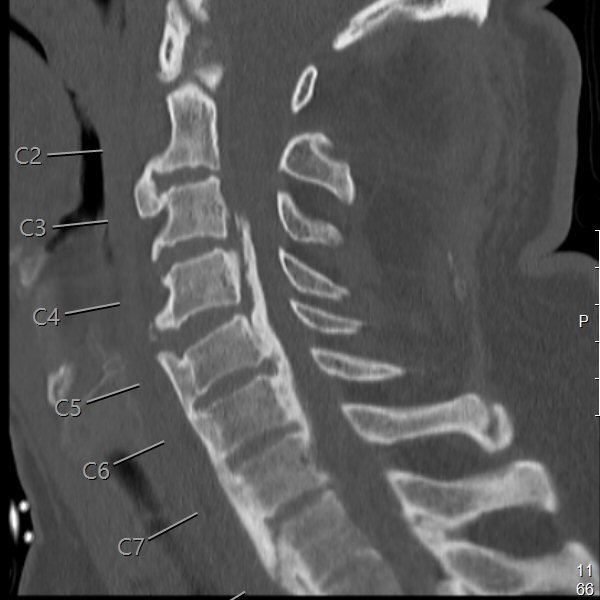

Notera att vid Bechterews sjukdom eller DISH-förändringar så blir frakturer ofta instabila. MR-undersökning krävs ofta inför operationsbeslut.

Instabil fraktur mellan C5 och C6 i Bechterew-rygg där ryggmärgen kapats nästan helt.